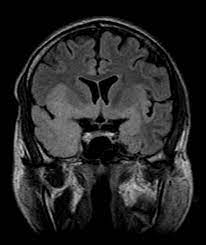

The characteristic feature of hse is hemorrhagic necrosis of the temporal lobe. Severe edema, petechial hemorrhage, and massive hemorrhagic tissue necrosis can be seen on gross specimens. Because early diagnosis is possible in more cases of herpes simplex encephalitis (hse) as a result of the high sensitivity of mri, now widely available, a larger number of patients are receiving appropriate treatment with iv acyclovir. Herpes simplex encephalitis typically manifests in older adults (about 50% of cases) with headache, fever, altered sensorium, and even seizure. Herpes simplex virus (hsv) is the most common cause of acute fatal sporadic encephalitis, with a particular predilection for the limbic system. that appeared in a recent issue of clinical infectious diseases. It is usually bilateral but asymmetrical. This lesion was seen in all patients as the disease progressed.

It is usually bilateral but asymmetrical. This lesion was seen in all patients as the disease progressed. Two subtypes are recognised which differ in demographics, virus, and pattern of involvement. The lateral temporal lobe and insula are less commonly involved, whereas the basal ganglia, in contrast, are frequently involved, helpful in distinguishing it from hsv encephalitis which characteristically spares the basal ganglia 8. However, mimics of hse, including other infections and increasingly recognized autoimmune causes, have been described in cases of tl encephalitis. Severe edema, petechial hemorrhage, and massive hemorrhagic tissue necrosis can be seen on gross specimens. Because early diagnosis is possible in more cases of herpes simplex encephalitis (hse) as a result of the high sensitivity of mri, now widely available, a larger number of patients are receiving appropriate treatment with iv acyclovir. A feasibility study of quantifying longitudinal brain changes in herpes simplex virus (hsv) encephalitis using magnetic resonance imaging (mri) and stereology. In addition, it was observed in various pathological conditions: Limbic encephalitis, mca ischaemia, tumours, effects of seizures) hyperintense t2 signal in the medial temporal lobes, inferior frontal lobes and insula basal ganglia are usually spared He was managed with intravenous acyclovir 30mg/kg and supportive therapy. We describe the spectrum of etiologies associated with temporal lobe (tl) encephalitis and identify clinical and radiologic features that distinguish herpes simplex encephalitis (hse) from its mimics. Herpes simplex virus (hsv) is the most common cause of acute fatal sporadic encephalitis, with a particular predilection for the limbic system.